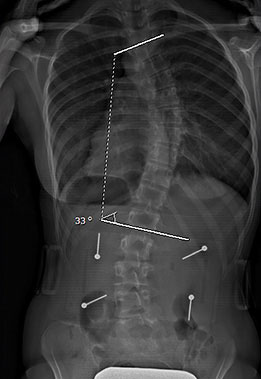

Le cas d'une adolescente âgée de 12 ans et 9 mois (Risser 0) au début du traitement.

Cette jeune fille, dont la photographie montre une difformité importante du dos, souffre d’une scoliose déjà sévère dont la courbe atteint 42° (angle de Cobb) au début du traitement.

Dès l'installation du SpineCor®, on note une réduction de la courbure grâce à l'action dynamique des bandes élastiques malgré une scoliose très importante.

Après 30 mois de traitement, la scoliose est stabilisée à 33° et la croissance terminée. Il est normal avec une courbure d'amplitude aussi marquée de remarquer une légère perte de correction par rapport au premier jour du traitement, car la colonne vertébrale de la patiente a continué de grandir durant le traitement et la courbe d'évoluer. Quand on débute plus jeune le traitement sur des scolioses de moindre amplitude, il est souvent possible d'éviter ces phases d'aggravation.

Mais au final, la dernière photographie prise après le sevrage du traitement montre clairement que la posture de la jeune fille présente un aspect beaucoup plus normal et symétrique qu'au début. Grâce à SpineCor®, l'esthétique de son dos s'en trouve améliorée encore plus que la correction réelle de sa courbe, ce qui aura inévitablement un effet positif direct sur son image de soi.